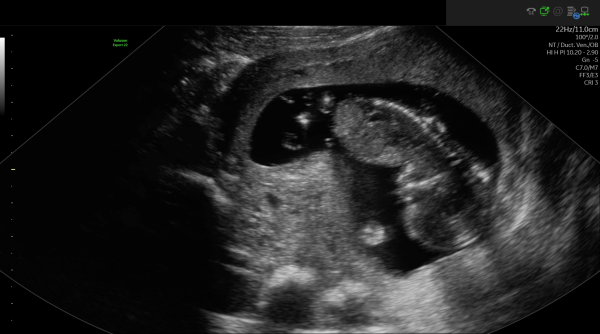

Någon som vågar gissa? V 11+4

Skulle gissa på kille 💙

Hej! Kan ni gissa på min? :) Tagen v. 11+3 så kanske lite tidigt men vill ändå höra gissningar.

gammal tråd men någon som vill gissa?

Kan tillägga att bilderna är från kub vecka 13+1

Det skulle vara roligt att veta vad kubteorin säger om kön. V 13+1